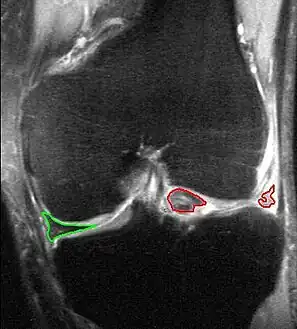

Bucket-handle tear of the lateral meniscus (red). Medial meniscus intact (green). MRI, coronal T2 *-weighted GRE sequence.

Bucket-handle tear of the lateral meniscus (red). Medial meniscus intact (green). MRI, coronal T2 *-weighted GRE sequence.

X-ray images (normally during weightbearing) can be obtained to rule out other conditions or to see if the patient also has osteoarthritis. The menisci themselves cannot be visualised with plain radiographs. If the diagnosis is not clear from the history and examination, the menisci can be imaged with magnetic resonance imaging (an MRI scan). This technique has replaced previous arthrography, which involved injecting contrast medium into the joint space. In straightforward cases, knee arthroscopy allows quick diagnosis and simultaneous treatment. Recent clinical data shows that MRI and clinical testing are comparable in sensitivity and specificity when looking for a meniscal tear.